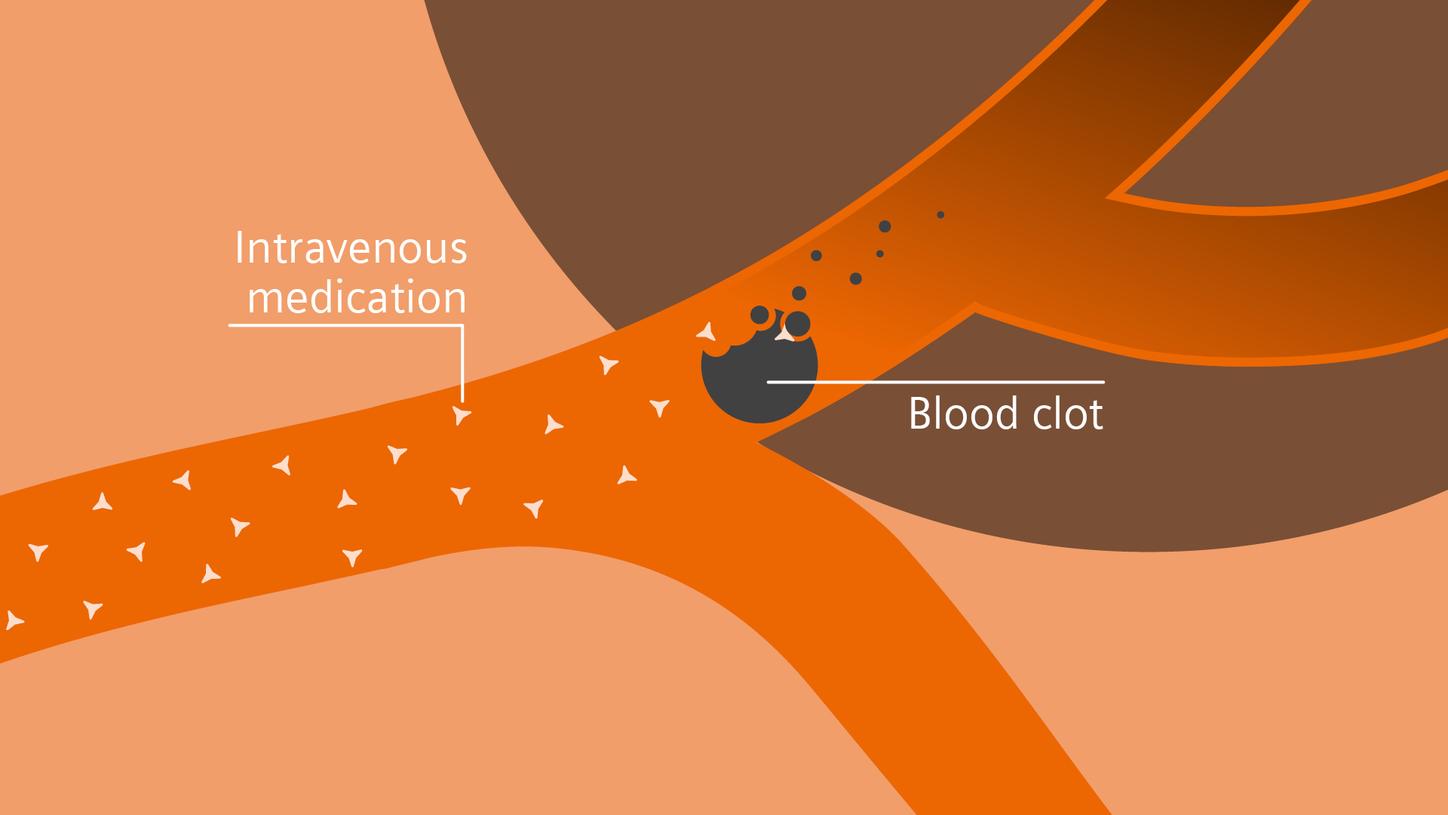

Treatment

In stroke care, time is brain. Rapid and accurate imaging is crucial to assess the extent of brain injury and guide immediate treatment. Angiography, MRI, CT, ultrasound, and lab diagnostics are essential tools in identifying stroke type, location, and severity. Advances in imaging technology now allow for even faster acquisition, improved resolution, and enhanced visualization of brain tissue and blood vessels. Innovations such as perfusion imaging, real-time vascular mapping, and AI-assisted diagnostics are transforming stroke workflows and enabling precise, timely interventions.